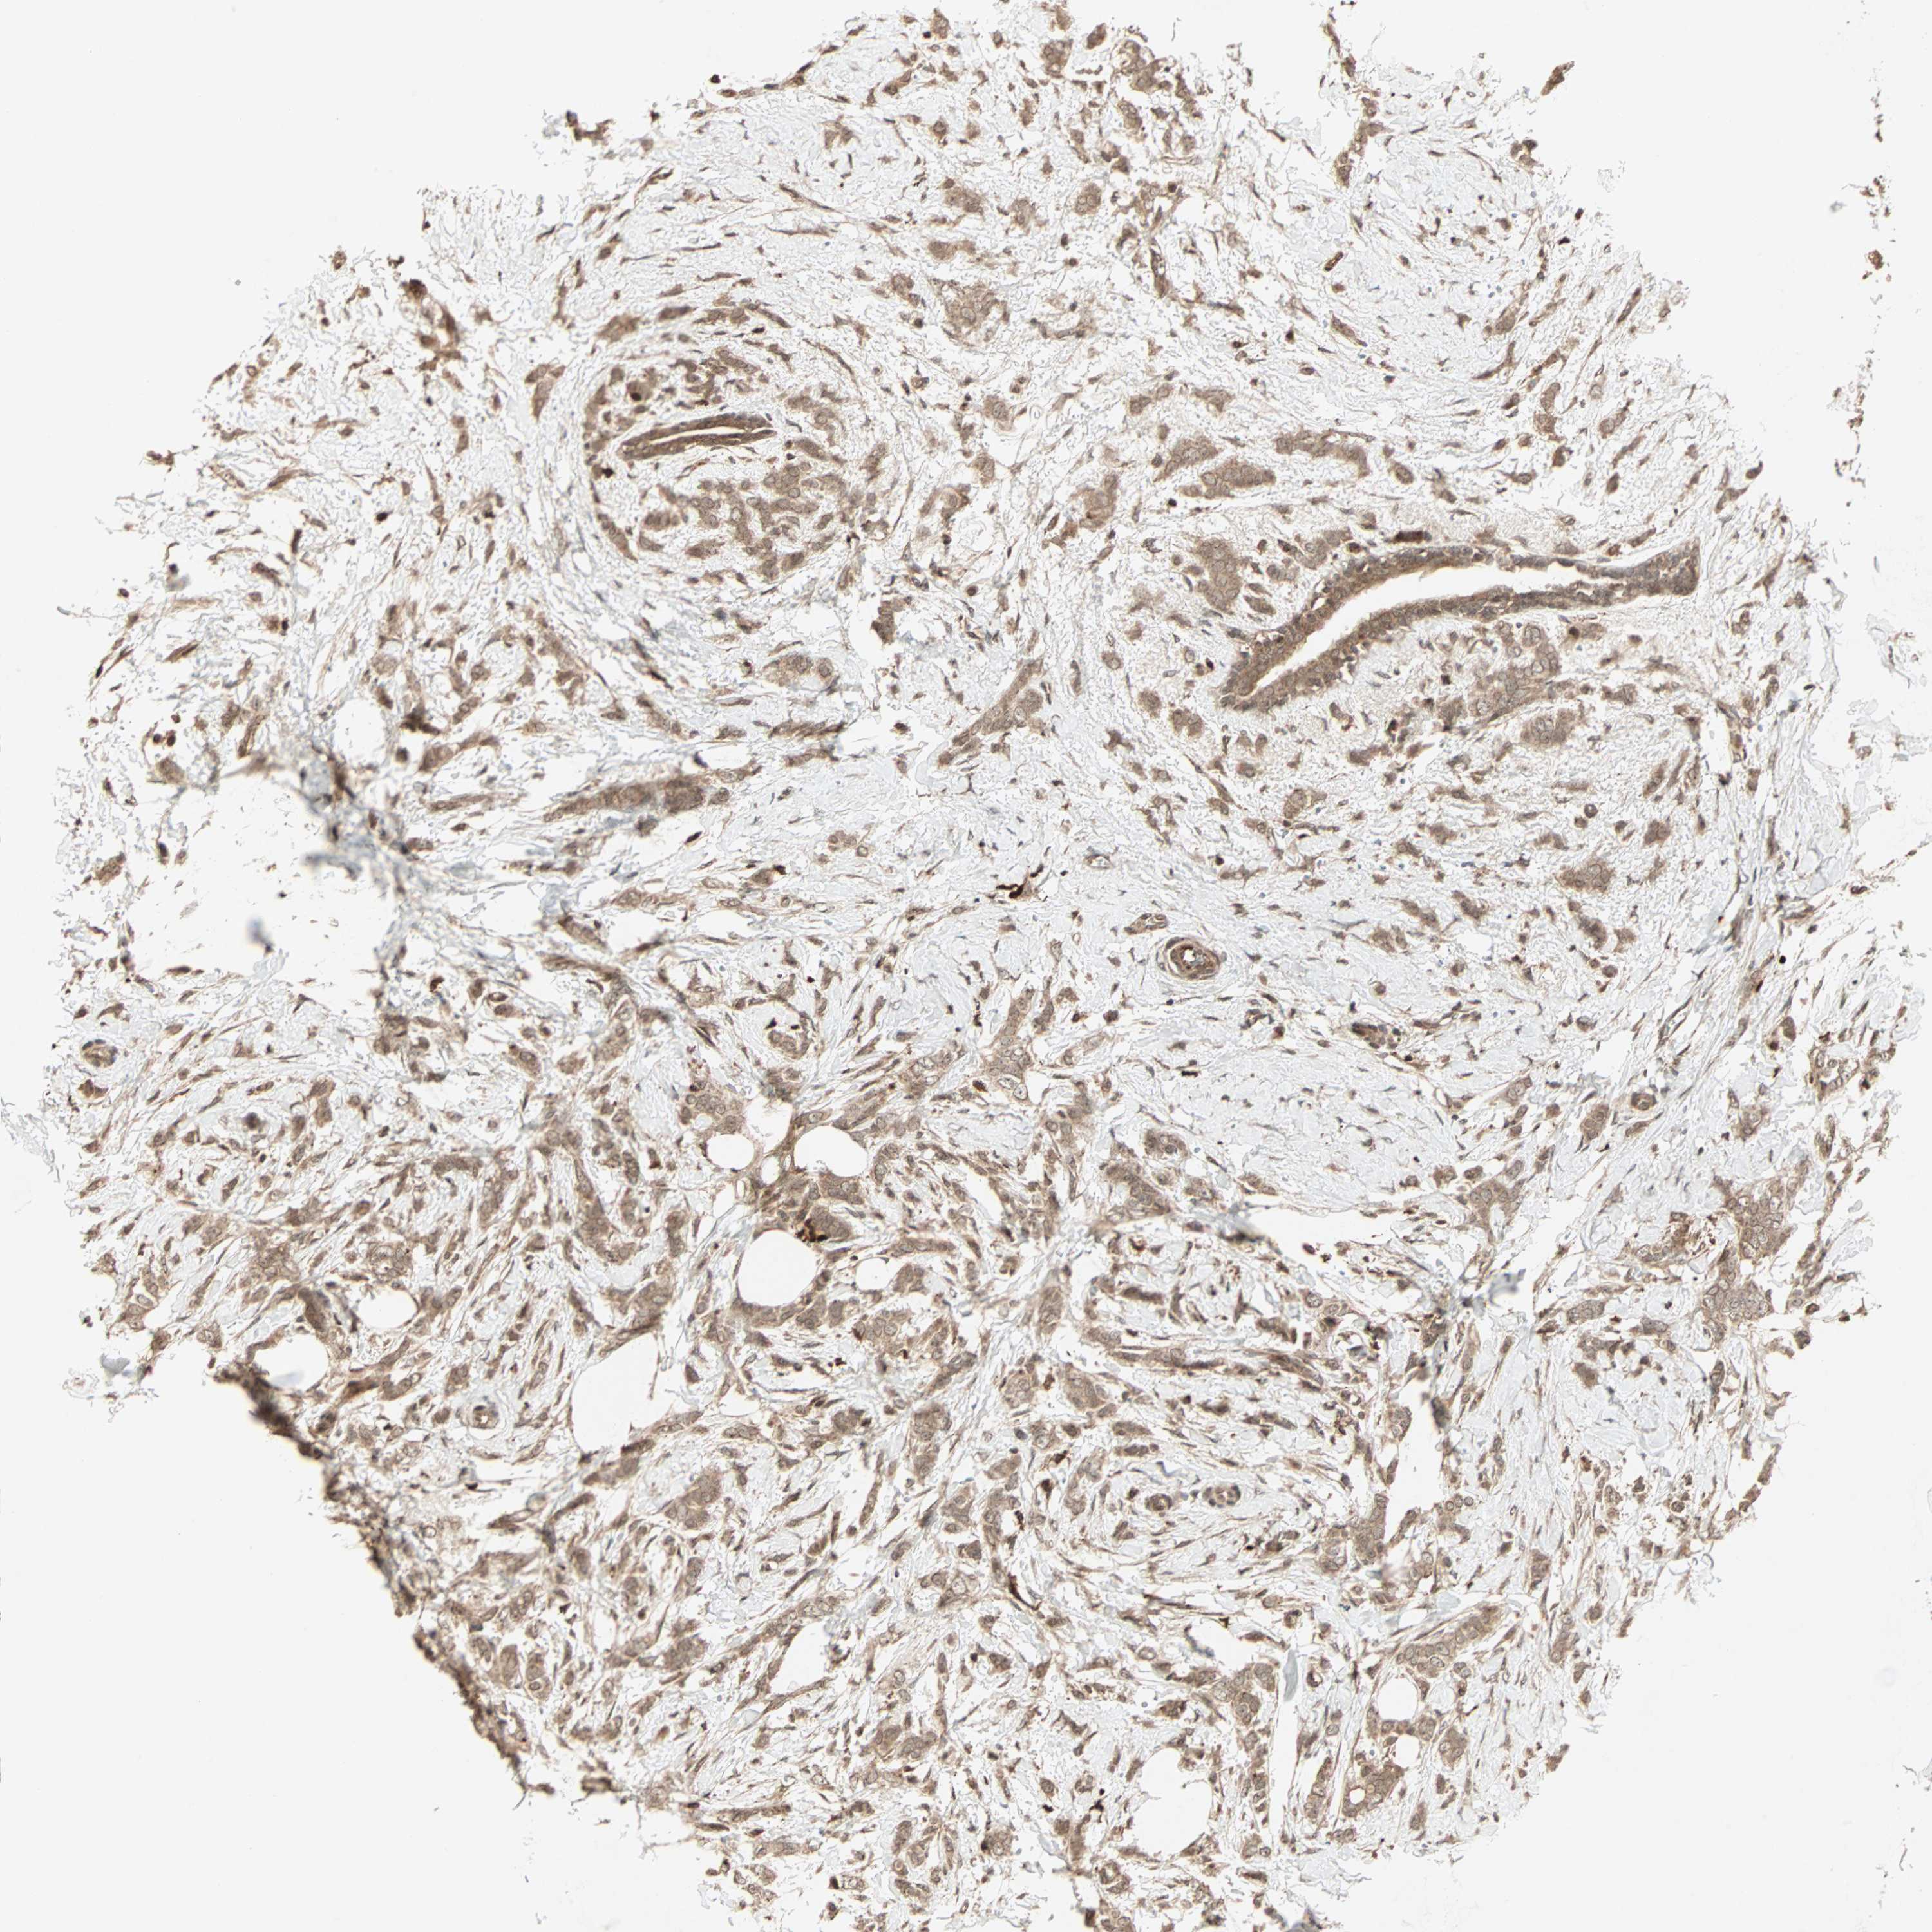

BRCA TCGA BRCA VALIDATION PROTEIN EXPRESSION

ANTIBODIES

AND

VALIDATION